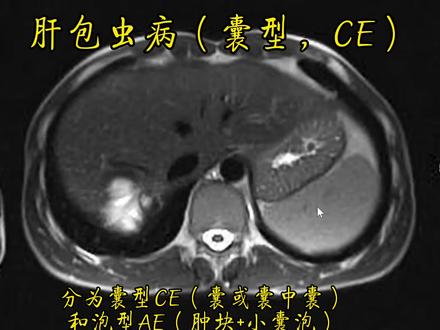

肝包虫病如果在早期的话,一般他是没有症状,所以我们一般人也发现不了,那如果等他有症状的时候,这个时候往往是处在晚期了,这种晚期的单纯靠这种我们所口语说的打虫药啊,实际上不是我们 治疗那个陶虫,这种打虫药是有专门的这个药物,他本身来说呢,他的药性并没有那么强,而且他有很强的这个肝损害的作用,所以一旦发生了这种情况之后, 首先还是要进行手术切除,然后术前术后为手术期进行一个口部药物的这样一个辅助,或者是预防的这样一个治疗。

包虫病是什么?包虫病又称急球幼病,是人感染急球掏虫的幼虫而导致的慢性寄生虫病。包虫病在我国西部牧区是一种十分常见的援助共患寄生虫病, 严重危害牧民的身体健康。俗话说病从口入,人们患包虫病是因为不小心误食了虫卵,包虫卵我们用肉眼是看不见的,那么人类为什么会误食包虫卵呢?其实包虫的最终阻阻并不是人,而是狼、虎、狗这些动物,其中与人类接触最多的狗正是传播包虫病的元凶。 包虫的成虫一般寄宿在狗的小肠里,会随狗的粪便一起排出,污染草场的土壤和水源,再通过被污染的水和草场间接传染给人。被包虫病感染的患者会出现肚子胀痛、不想吃东西、恶心、变白、皮肤变黄等症状。有以上症状的小伙伴们应该到医院做一个检查,还有 一部分人没有任何症状,需要定期做健康体检才能发现,目前可以通过 b 超和抽血化验检查出是否感染包重病。 接下来听听亳州人民医院肝胆疑皮外科主任邹胜海怎么说。随着国家投入大量的这个人流率,现在包括整体呢,是挺减少的趋势的,但是一个值得我们警惕的现象呢,在我们亳州地区这两年这个儿童的发病率,还有这个城市里的这个发病率呢? 呃,没有减少,甚至还增增加血型,这个是非常值得我们警惕的,所以我们一定要做好一个。第一是甲醛的管理,因为我们包虫为主,都是通过狗的这个粪便来传播这个虫卵导致的这个, 所以我们做好家属的管理非常重要。第二个呢,就是我们要做好严格的个人卫生,我们卫生习惯要做好,呃, 还有可能这个尽量减少生的的生死的啊。所以说去健康宣传非常重要,如果说我们健康体检发现了整个的保守力,我们及时到月经去诊保守病呢,诊室治疗的心理 非常成熟,也很规范,如果小的高手呢?我们通过这个和服药,大多数我们有手术治疗手段,包括开刀手术啊,妇产病,微创等等 都非常成熟。当然得了包虫病的患者无比接受隔离治疗,因为人与人之间是不会传染包虫病的,既然包虫病的根源在狗,那么避免与狗尤其是流浪犬接触,就能大大减少感染包虫病的机会。家养的狗也需要定期投药驱虫,并将犬分及时清理和深埋。 另外养成良好卫生习惯,勤洗手不仅能消除许多致病菌,包虫的虫卵也会被清水冲走。下面让我带大家一起学习一下七步洗手法,请大家跟着我一起做。第一步,掌心对掌 心,相互揉搓。第二步,掌心对手背,手指交叉相互揉搓。第三步,掌心对掌心,手指交叉相互揉搓。第四步,弯曲指关节在掌中相互揉搓。 第五步,拇指在掌中转动,相互揉搓。第六步,指尖在掌中相互揉搓。第七步,清洗腕部,流动水冲洗双手,纸巾擦干。大家学会了吗?